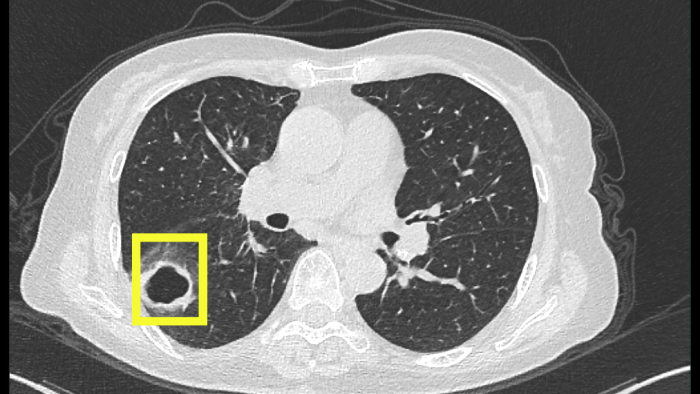

最開始以為只是普通感冒,但柴阿姨自行吃藥后并沒有好轉(zhuǎn)。感到焦慮的柴阿姨便到當(dāng)?shù)蒯t(yī)院就診,經(jīng)肺部CT檢查發(fā)現(xiàn),肺部出現(xiàn)空洞病灶。

當(dāng)?shù)蒯t(yī)院認(rèn)為有可能是肺結(jié)核,柴阿姨忐忑不安地來到衢州市人民醫(yī)院(溫州醫(yī)科大學(xué)附屬衢州醫(yī)院)感染科就診。

迷團(tuán)終于解開,原來引起柴阿姨肺部空洞的“罪魁禍?zhǔn)住辈皇欠谓Y(jié)核,而是真菌感染。

該患者是以咳嗽伴肺部空洞性病灶來就診的,最常見的病因是結(jié)核分枝桿菌引起的肺結(jié)核,但做了結(jié)核的相關(guān)檢查均未提示肺結(jié)核。而當(dāng)常規(guī)的檢驗(yàn)技術(shù)未發(fā)現(xiàn)病原菌時(shí),氣管鏡檢查及肺泡灌洗液的宏基因組測序就非常重要,可以讓患者少走很多彎路,使診斷及時(shí)明確,讓患者得到精準(zhǔn)治療。